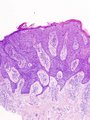

|

Squamous cell carcinoma. H&E stain. | |

Squamous cell carcinoma of the skin is a common malignant neoplasm of the skin.

Microscopic

- G1 - well differentiated - easily recognizable as squamous, abundant keratinization.

- G2 - moderately differentiated - keratinization focal (typically limited to keratin pearls, individual cells or horn cysts).

- G3 - poorly differentiated - difficult to establish as squamous.

- G4 - undifferentiated or anaplastic.